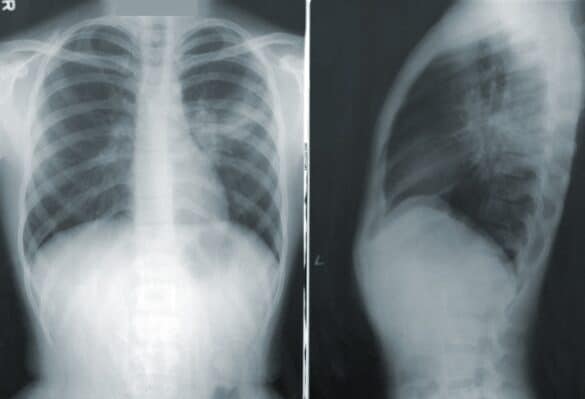

Choroby płuc wywołane pyłem metali twardych

Ciągłe wdychanie pyłów metali twardych prowadzi do chorób płuc. Jak pomóc pracownikom, którzy każdego dnia mają kontakt z chorobotwórczymi pyłami?…